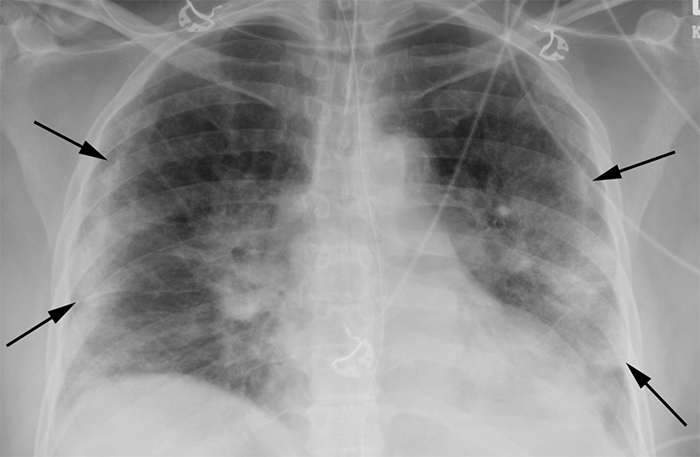

The radiologists conducted a retrospective study of nearly 400 persons under investigation (PUI) for COVID-19 in New Orleans. They reviewed the patients’ chest x-rays along with concurrent reverse-transcription polymerase chain reaction (RT-PCR) virus tests. Using well-documented COVID-19 imaging patterns, two experienced radiologists categorized each chest x-ray as characteristic, nonspecific, or negative in appearance for COVID-19.“The presence of patchy and/or confluent, band-like ground glass opacity or consolidation in a peripheral and mid-to-lower lung zone distribution on a chest radiograph is highly suggestive of SARS-CoV-2 infection and should be used in conjunction with clinical judgment to make a diagnosis,” says Bradley Spieler MD, Associate Professor of Diagnostic Radiology and Vice Chairman of Research in the Department of Radiology at LSU Health New Orleans School of Medicine.